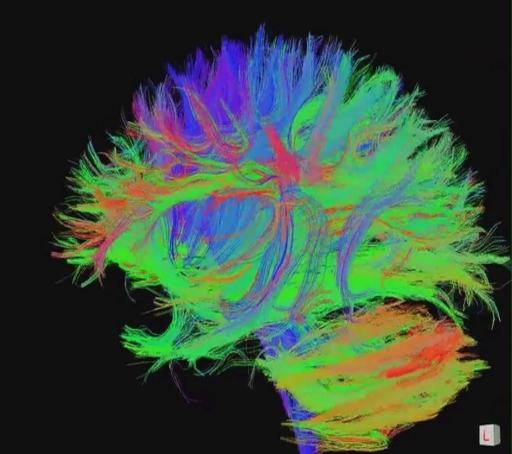

What is TMS? How does TMS work? MagVenture TMS Therapy